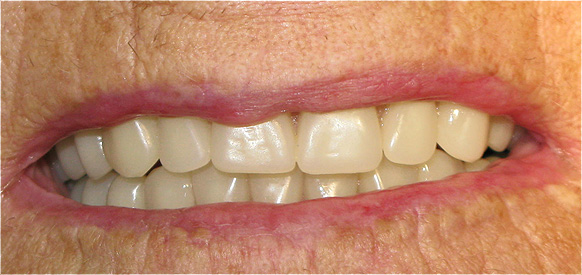

Caso 4 - Agenesia dos incisivos laterais superiores - tratamento ortodôntico para encerramento de diastema e implantes

![]() |